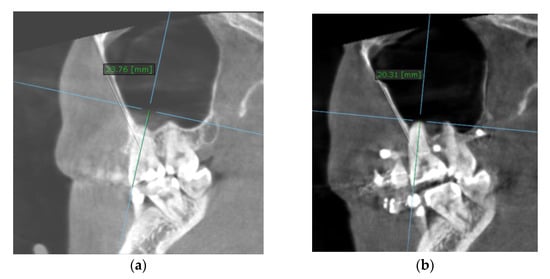

To calculate the amount of performed molar intrusion, the difference of the linear distance from the mesiobuccal cusp of the maxillary first molar to a custom palatal plane (CPP) was measured on CBCT images before and after intrusion mechanics. The CPP was defined by the following three points: ANS, and the lowest points of the pterygoid hamulus on the left and right sides. The measurements were performed by one maxillofacial surgeon and one orthodontist, twice, and mean values were considered (Table 4).

Table 4.

The CBCT measurements before and after intrusion at the level of upper first molar and upper first premolar.

The measurement method is shown in Figure 7.

Figure 7.

Intrusion amount, at the level of the mesiobuccal cusp of the right upper first molar (the distance between the cusp tip and CPP): (a) before intrusion: 23.76 mm; (b) after intrusion: 20.31 mm.